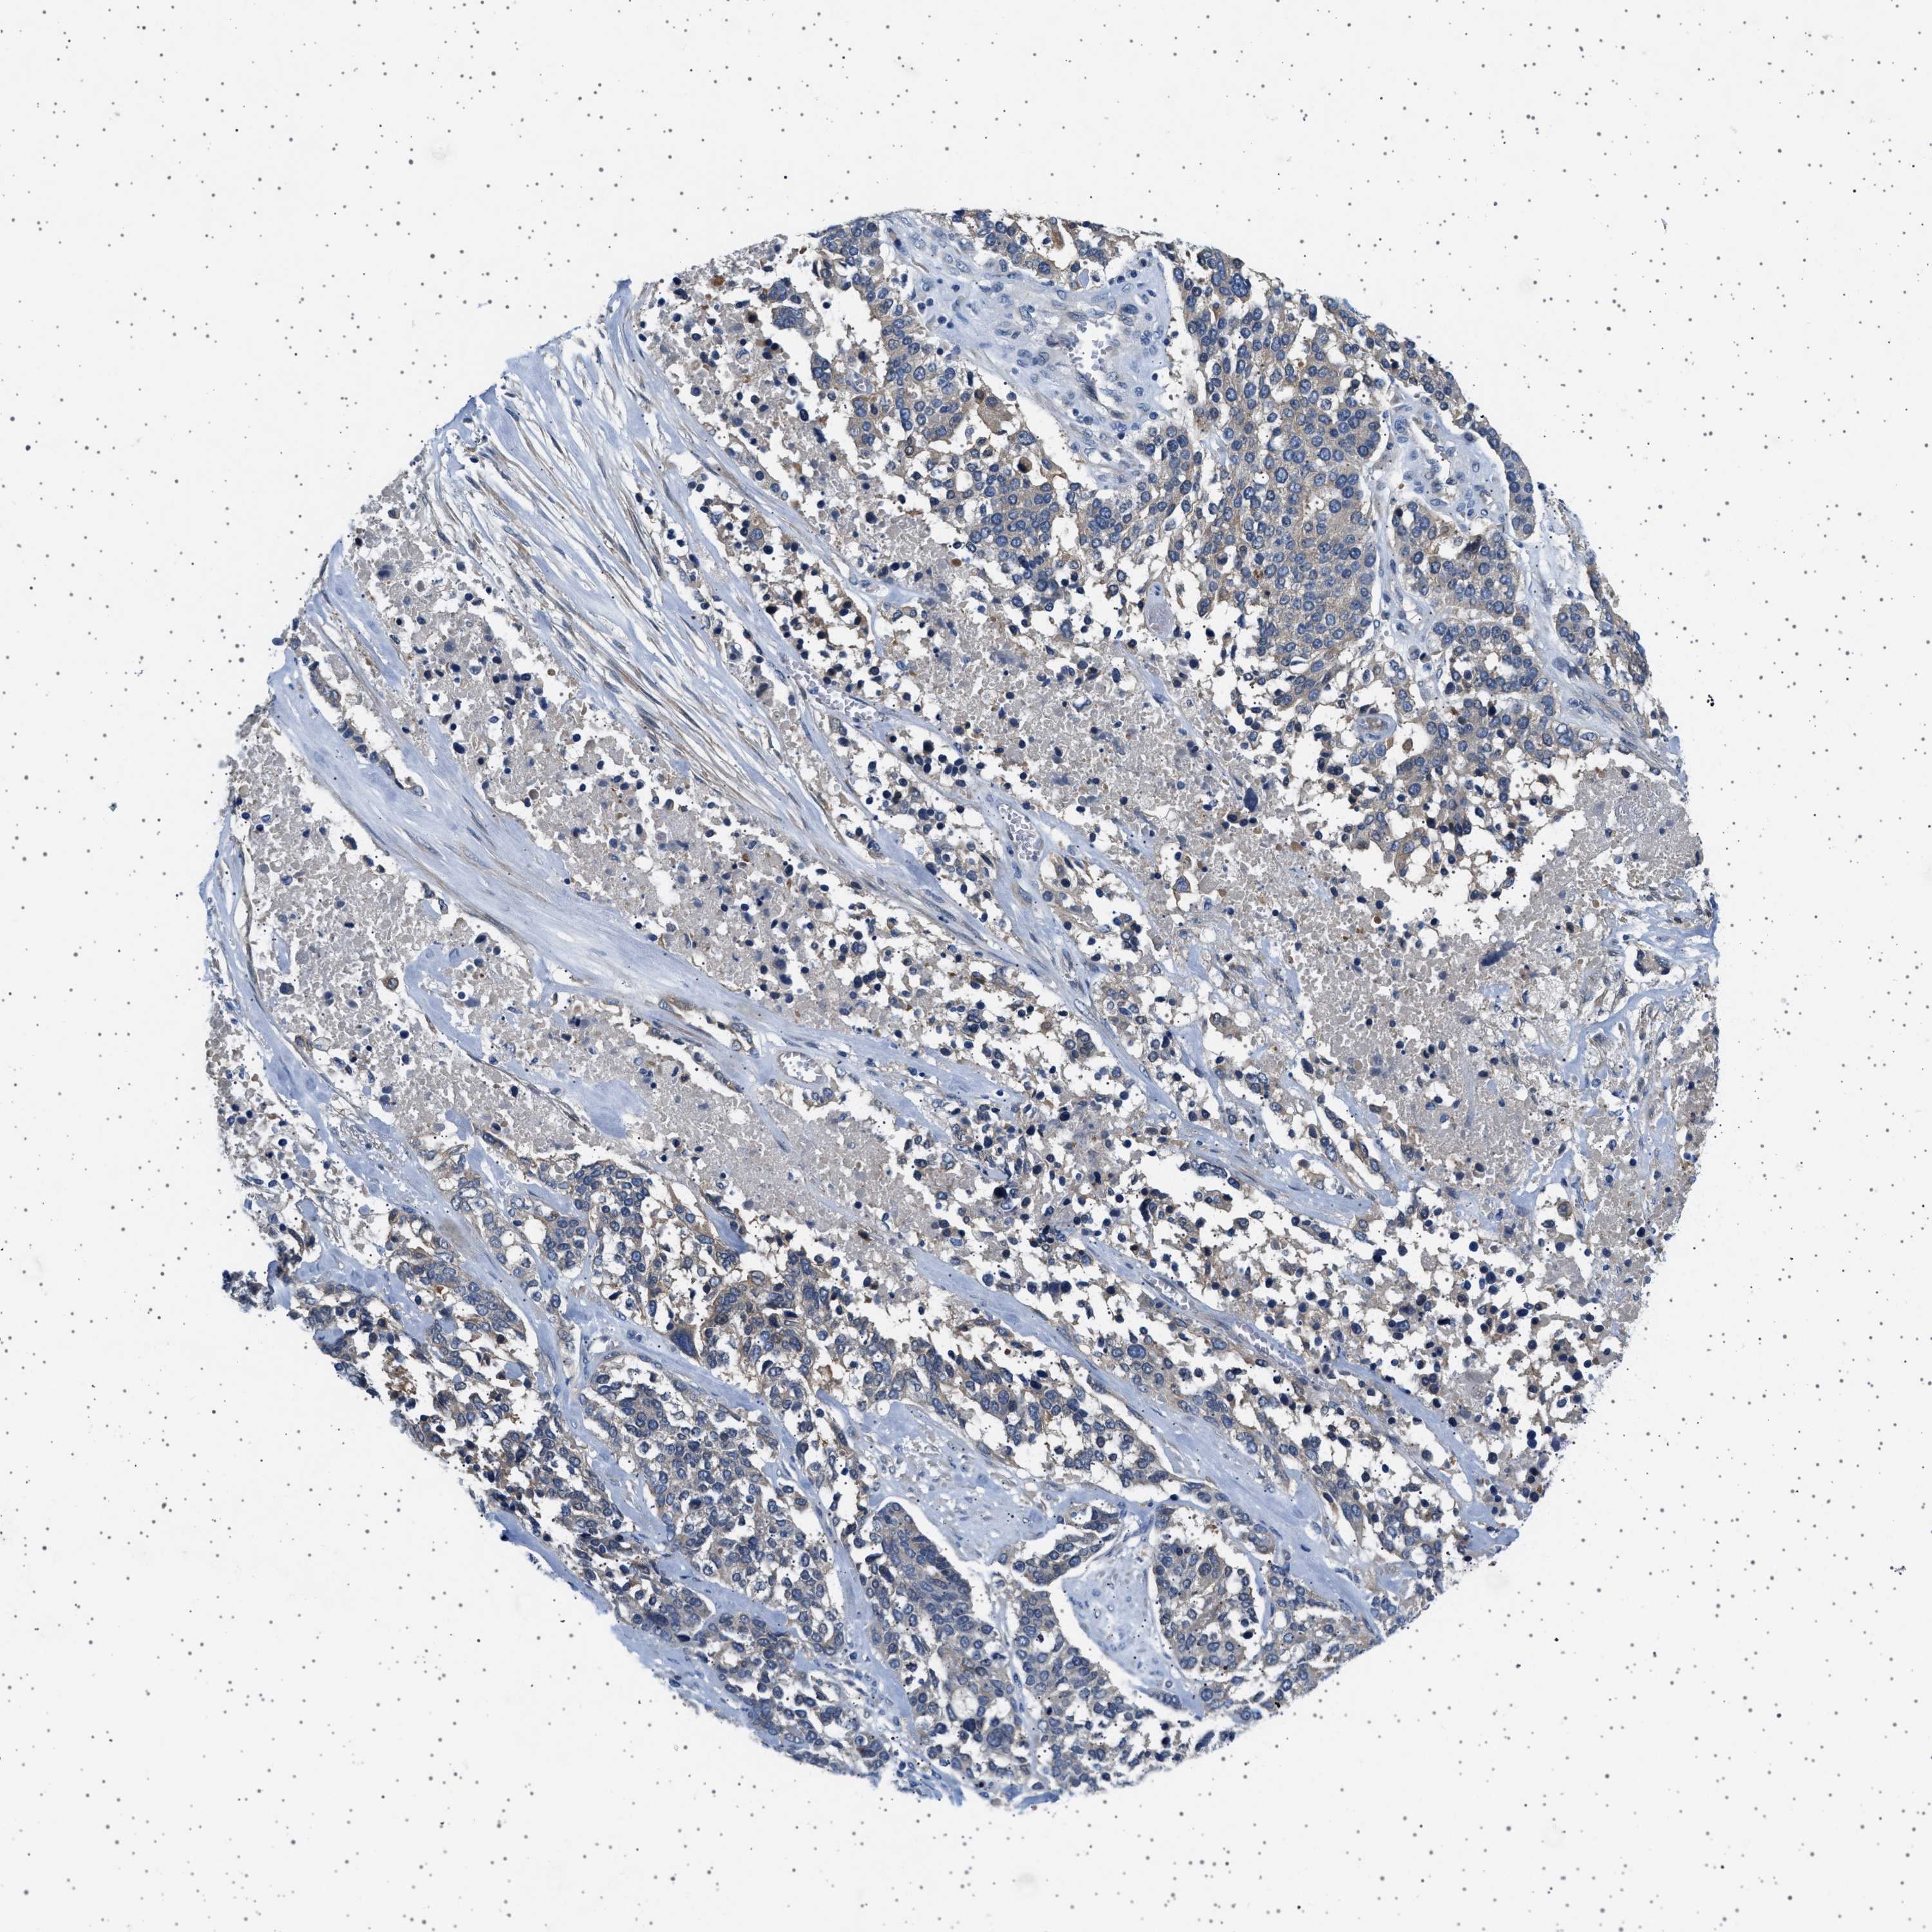

OVARIAN CANCER - Protein expressioni

A mouse-over function shows sample information and annotation data. Click on an image to view it in a full screen mode. Samples can be filtered based on level of antibody staining by selecting one or several of the following categories: high, medium, low and not detected. The assay and annotation is described here.

Note that samples used for immunohistochemistry by the Human Protein Atlas do not correspond to samples in the TCGA dataset.

Antibody stainingi

Antibody staining in the annotated cell types in the current human tissue is reported as not detected, low, medium, or high, based on conventional immunohistochemistry profiling in selected tissues. This score is based on the combination of the staining intensity and fraction of stained cells.

Each image is clickable and will lead to virtual microscopy that enables deeper exploration of all samples and also displays staining intensity scores, fraction scores and subcellular localization as well as patient and tissue information for each sample.

Antibody HPA018096

Cystadenocarcinoma, serous, NOS